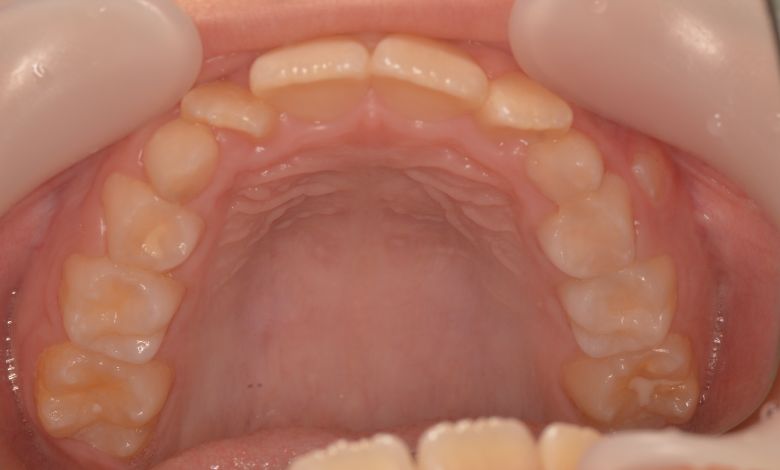

歯列全体に強いガタつき(叢生)が見られ、特に上下の前歯は重なりが大きく、見た目にも咬み合わせにも

大きな不調和がありました。歯列弓はV字型に狭く、他院では抜歯を伴う矯正治療が提案されていました。

歯列弓はV字型に狭く、左右の犬歯が唇側に大きく転位している状態

歯列弓はV字型から自然でゆったりとしたU字型へと広がり、唇側に転位していた犬歯も正しい歯列内に整列されています。

上下の前歯に強い重なりが見られます。特に上顎犬歯と下顎前歯のズレが顕著で、自然な咬合が形成されていない

上下の前歯の重なりや段差は完全に解消され、咬合関係も安定してる。自然なスマイルラインが形成され、口元の印象も大きく改善された

前歯部では3歯が大きく重なり、ねじれや傾斜も伴っている。歯列弓は狭く、U字型から逸脱した非対称な形態

歯列弓の側方拡大により適切なスペースが確保され、歯が綺麗に並んでいます

当院では抜歯を行わず、歯列弓を広げてスペースを確保する治療を選択。歯並びは自然なU字型へと整い、前歯の重なりも解消されました。咬み合わせが改善され、見た目の美しさはもちろん、咀嚼機能や清掃性の向上といった機能面でも良好な結果が得られています。